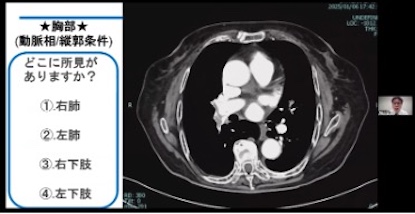

臨床講演では、「症例から学ぶ腹部領域~今年の冬は腹部疾患を学ぼう~」では、初の試みとしてZoomの投票・クイズ機能を活用しました。各自の画面に投票タブを表示して、全5問の症例クイズに回答していただきました。

症例①では、船橋総合病院の本澤さんより、肝臓の症例が3例提示されました。臨床現場で遭遇する機会の多い肝細胞癌(HCC)や肝血管腫について、造影濃染パターンや肝区域分類を実際のCT画像と照らし合わせながら解説していただきました。疾患の判別だけでなく、病変が存在する区域まで意識して観察することの重要性が伝わる内容であったと思います。

臨床講演では「症例から学ぶ血管領域 ~今年の夏は血管疾患を学ぼう~ 」と題して症例検討を行いました。チャット機能を活用して参加者の方に全6問の症例クイズに挑戦していただきました。(画像②)

症例①では津田沼中央総合病院 小西さんより、大動脈解離の症例を3例提示していただきました。

症例の中には別の疾患に気を取られて見落としていた例もあり、注意深く画像を観察することの重要性を伝えられたのではないかと思います。

症例②では東川口病院 小島さんより、肺塞栓症、下肢静脈血栓症の症例を提示していただきました。

ヨード密度画像を作成して肺灌流の状態を分かり易く描出したり、仮想単色X線画像によって下肢静脈の造影効果を増強したりするDualEnergy CTを活用されていました。

症例③では上尾中央総合病院 吉田さんより、大動脈瘤、破裂の症例を2例提示していただき、造影CT検査における撮影を開始するタイミングの重要性を述べられ、モニタリング位置の工夫を解説していただきました。(画像③)